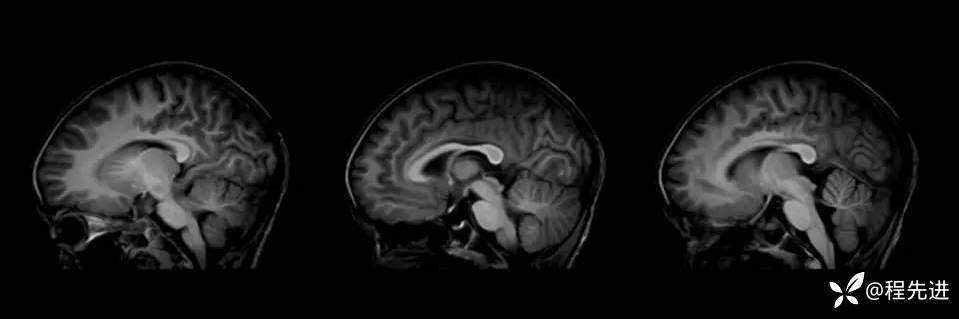

患者性别:女

患者年龄:3岁

主诉:间断呕吐2天,伴腹泻1天,惊厥1次

现病史:2天前进食后呕吐,非喷射状,1天前出现腹泻,每日4-5次。入院2小时前出现抽搐发作

辅助检查:便常规轮状病毒(+)

伴可逆性胼胝体压部病变的轻度脑炎 (7)